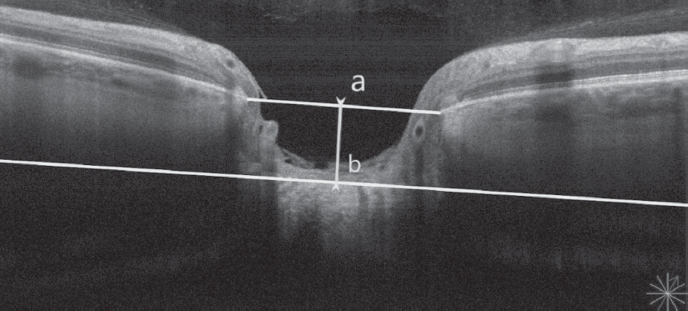

In all subjects, TLC and DLC were measured using the OCT RS-3000 Advance (Nidek, Japan) in an enhanced depth imaging mode, using the DISC RADIAL protocol and calculating the average value of these parameters from three consecutive measurements. DLC (posterior LC displacement) was defined as the perpendicular straight line drawn between the center of this line and the front surface of the LC (a–b). TLC was defined as the segment between the anterior and posterior surfaces of the LC in its central part (c–d) (Fig. 1, 2). To measure the LC parameters, a line connecting the end points of the Bruch’s membrane was used as a base plane. The same OCT device was used to measure the central thickness of the cornea using a nozzle for the anterior segment of the eye. It was additionally measured using a Pentacam HR device (Oculus, Germany).

Fig. 1. Lamina cribrosa depth measurement (a–b) by EDI (Enhanced Depth Imaging) mode of Nidek RS-3000 Advance

Рис. 1. Измерение глубины решётчатой пластинки (a–b) с помощью оптического когерентного томографа Nidek RS-3000 Advance в режиме увеличенной глубины изображения (EDI)